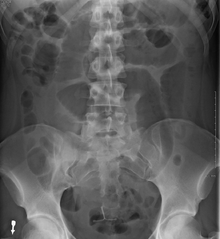

Coffee bean sign in a patient with sigmoid volvulus

After taking a thorough history, the diagnosis of colonic volvulus is usually easily included in the differential diagnosis. Abdominal plain x-rays are commonly confirmatory for a volvulus, especially if a "bent inner tube" sign or a "coffee bean" sign are seen. These refer to the shape of the air filled closed loop of colon which forms the volvulus. Should the diagnosis be in doubt, a barium enema may be used to demonstrate a "bird's beak" at the point where the segment of proximal bowel and distal bowel rotate to form the volvulus. This area shows an acute and sharp tapering and looks like a bird's beak. If a perforation is suspected, barium should not be used due to its potentially lethal effects when distributed throughout the free infraperitoneal cavity. Gastrografin, which is safer, can be substituted for barium.